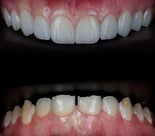

COROAS E FACETAS DE PORCELANA UNITÁRIAS

As coroas ou lentes de porcelana também tem ampla indicação em casos unitários : dentes fraturados, escurecidos após tratamentos de canal, alterações de forma e manchas que não respondem ao clareamento, são exemplos de situações em que precisamos harmonizar esse novo dente com os vizinhos.

Espelhar um dente vizinho com uma nova coroa ou faceta de porcelana, é um procedimento altamente técnico, que requer a habilidade e experiência de um dentista estético e de um laboratório qualificado.